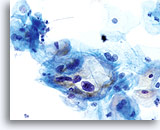

En raison de leur morphologie, les cellules issues de lésions de bas grade comptent parmi les anomalies intra-épithéliales les plus faciles à localiser et à identifier. En comparaison, les noyaux LSIL sont les plus grands et présentent un rapport N/C inférieur aux HSIL ou carcinomes. Ces cellules affichent une atypie nucléaire plus importante que les ASCUS (ce qui se traduit par une augmentation de la taille nucléaire, une irrégularité de la chromatine et une irrégularité de l’enveloppe nucléaire). Les noyaux peuvent occasionnellement ne pas être aussi hyperchromatiques que sur les frottis conventionnels, mais ils le sont toujours par rapport aux cellules normales environnantes. Les changements associés au HPV (par exemple, formation de cavités dans le cytoplasme) sont plus évidents grâce à la fixation liquide et à la technique de transfert, ce qui élimine la déformation des cellules associée à la méthode d’étalement conventionnelle. La méthode ThinPrep préserve mieux ces changements cellulaires, ce qui permet une meilleure distinction entre les véritables cavités cytoplasmiques induites par le HPV et les vacuoles bénignes/dégénératives et/ou les cellules malpighiennes glycogénées.

Comme il s’agit de cellules malpighiennes matures, elles gardent leur forme polygonale et conservent en partie leur taille normale. La taille des noyaux est au moins 3 à 4 fois supérieure à celle d’une cellule intermédiaire normale. En revanche, quand les changements associés au HPV sont évidents, les cellules peuvent être plus petites (quasiment parakératosiques), tout comme les noyaux (quelque peu pycnotiques) qui présentent en outre une binucléation et/ou multinucléation. Ces noyaux pycnotiques affichent en outre des caractéristiques anormales : hyperchromasie, augmentation de la taille par rapport à une cellule malpighienne superficielle normale, légère variation de la forme et de la taille, etc. Il est important d’insister sur le fait qu’une interprétation de LSIL/HPV implique des cavités cytoplasmiques nettes accompagnées de la morphologie nucléaire anormale décrite ci-dessus.